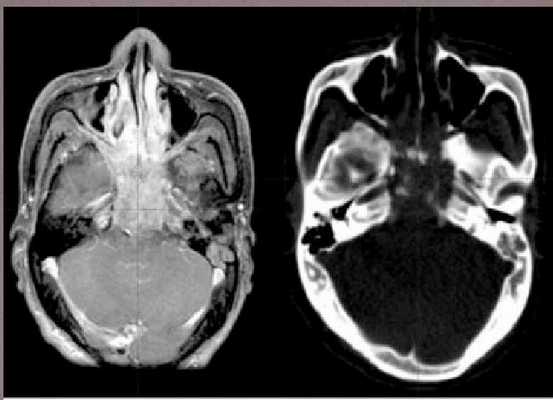

- КТ или МРТ. Томография показывает точную локализацию опухоли и ее распространение. Снимки визуализируют поражение межмышечной клетчатки нервов, разрушение костей основания черепа. Только по результатам магнитно-резонансной томографии удается выявить двустороннюю локализацию опухоли, в то время как другие методы исследования показывают наличие только на одной стороне лимфатических узлов. На поздних стадиях МРТ показывает прорастание опухоли в костные структуры, заглоточные лимфатические узлы и вещество головного мозга.

- МРТ (предпочтительно) и/или КТ носоглотки с контрастом — позволяют оценить распространение опухоли и определить стадию болезни.